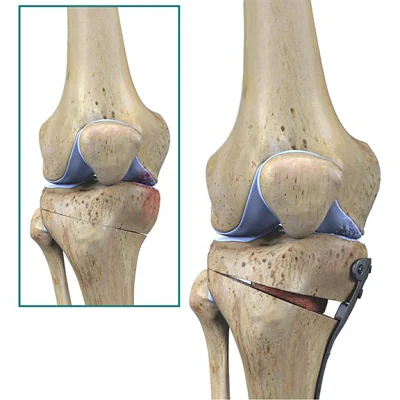

Who is a good candidate for HTO?

Good candidates are younger or middle-aged patients with pain on one side of the knee, bow leg deformity, or early arthritis. Active lifestyle and good bone quality are important factors.

What is the purpose of HTO?

The main purpose is to realign the knee joint, shift body weight away from the arthritic side, relieve pain, and preserve the natural joint. It allows patients to stay active longer before considering knee replacement.